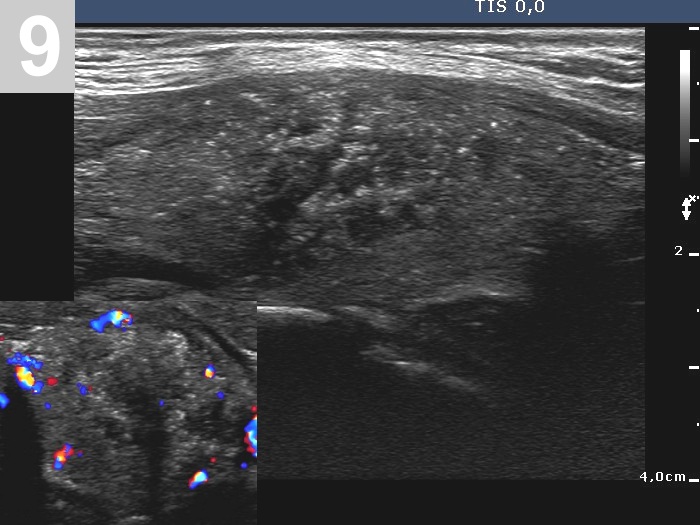

3 US of thyroid cancer

Pre- and postoperative ultrasound in thyroid cancers

Cases to be discussed on January 18, 2024